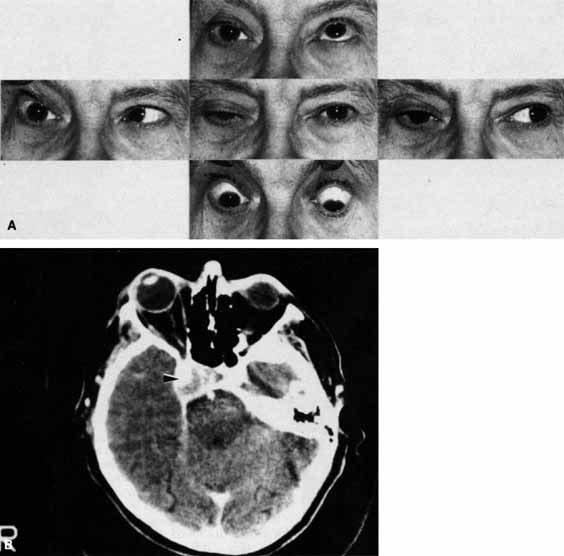

A 70-year-old woman presented with a 6-month history of progressive diplopia and ptosis. She demonstrated complete right third, fourth, and sixth cranial nerve palsies, and hypesthesia of cranial nerve V1 (Fig. 22A). The right pupil was dilated. Computed tomography (CT) disclosed an intracavernous aneurysm (see Fig. 22B).

Fig. 22 A. A 70-year-old woman with complete right third, fourth, and sixth cranial nerve palsies. Hypesthesia of cranial nerve V1 was also present. B. CT scan demonstrates an intracavernous aneurysm (arrow).

The so-called superior orbital fissure syndrome occurs when an infiltrative, inflammatory, or ischemic event occurs within the superior orbital fissure, but not in the orbital apex.4 A complete superior orbital fissure syndrome occurs when all the neurovascular components passing through the superior orbital fissure are damaged, producing a total ophthalmoplegia, ptosis, and anesthesia of cranial nerve V1 (see Fig. 22A). The pupil may be dilated, miotic, or midposition and fixed, depending on the balance of parasympathetic and sympathetic damage. The superior ophthalmic vein, best seen on CT, may be dilated if venous outflow from the orbit is obstructed. Clues to venous outflow obstruction are increased intraocular pressure, fullness of the upper eyelid, and hyperemia of the deep Tenon's vessels. Ophthalmoscopically, the retinal veins may be dilated. The effect of a lesion in the superior orbital fissure or the anterior cavernous sinus cannot be differentiated clinically (see Fig. 22B). When the posterior cavernous sinus becomes involved, hypesthesia of cranial nerve V2 may also be present.